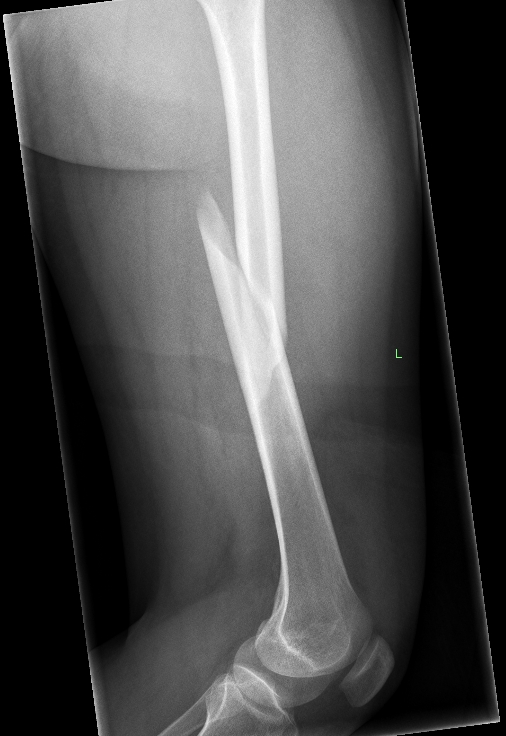

X-Ray Of A Patient Who Had A Long History Of Chewing And Gnawing Their Fingers To The Bone

This resulted in severe bacterial infections which had to be treated with multiple amputations amputations